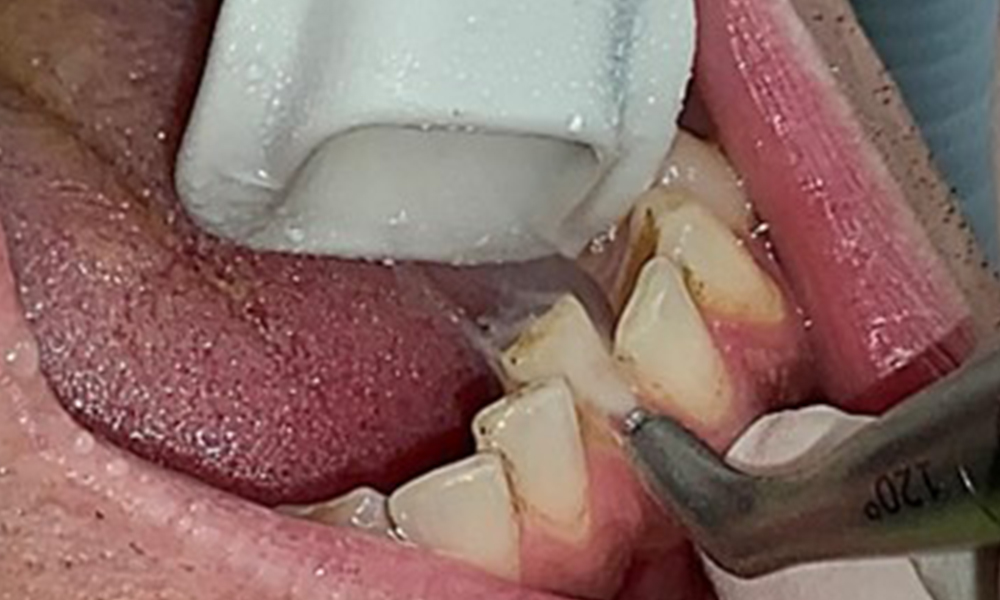

Due to the otherwise favourable general medical condition, the needs determined during the intraoral examination will be decisive for their treatment. It will be essential to periodically determine the probing depths. Gingival bleeding decreases in smokers, which is why the clinical diagnosis of periodontitis can only be made by probing (Fig. 7). Placing exclusive focus on the determination of bleeding indices may obscure existing periodontitis or gingivitis. (5)

Pocket probing (BOP) with depiction of tooth 36 lingual

Fig. 7 Pocket probing (BOP) with depiction of tooth 36 lingual, © Dr R. Krapf

The objective would be to control disease risk by removing supragingival and subgingival biofilm. The instruments can be selected based on patient needs. First, calculus and any concretions must be removed using ultrasonic and/or manual instruments (Fig. 10).

Use of a piezo-driven ultrasonic device in the lingual area near 36 (Proxeo Ultra, W&H, shown here)

Fig. 10 Use of a piezo-driven ultrasonic device in the lingual area near 36 (Proxeo Ultra, W&H, shown here), © Dr R. Krapf